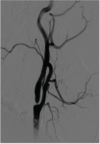

75

An 81-year-old man with hypertension, hyperlipidemia, and an ejection fraction of 45% presents with two episodes of transient right arm weakness over the past month. An angiogram is shown. Which of the following carries the lowest 30-day risk of stroke? Answers: A. Carotid artery angioplasty and stenting B. Carotid endarterectomy C. Atorvastatin therapy D. Aspirin and clopidogrel therapy E. Warfarin therapy

Correct Answer: Carotid endarterectomy